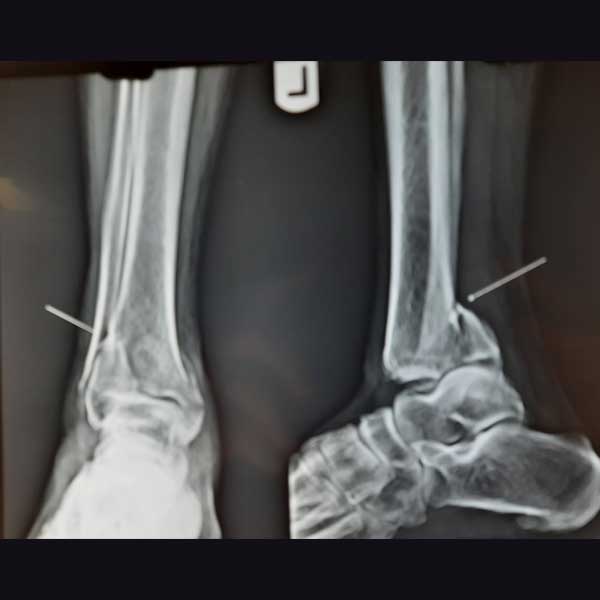

Case:19 Percutaneous fixation with Implants

A male patient, aged 78 years had been diagnosed to have a closed Pott’s fracture Left Ankle. He was treated operatively with Percutaneous fixation with Implants.

Pre-Operative

Post-Operative